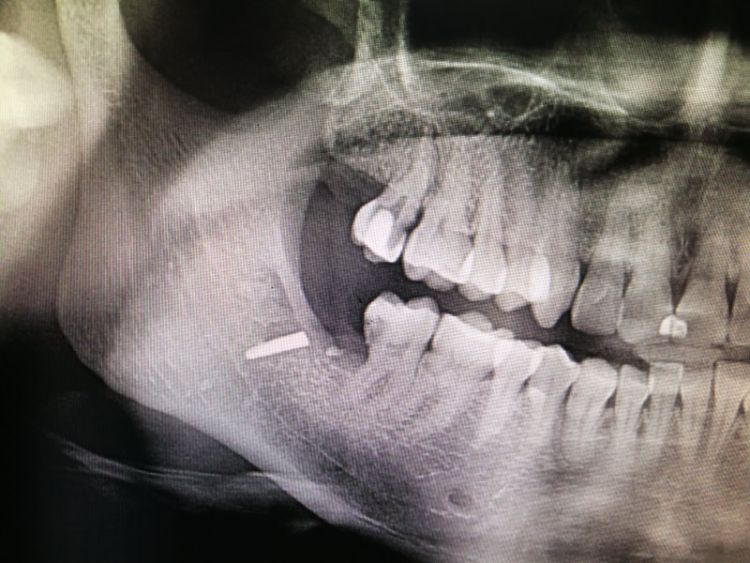

李女士口腔内的金属物。这一检查,把她吓了一跳。据其在松岗人民医院口腔科拍摄的x光片显示:她之前拔掉的智齿牙窝里,残留了两节金属物,并且已经没入很深,快要接近下颌神经管了。如果再深一点,可能会导致其面部神经损坏。“我听到,差点吓哭了。”李女士说。自己当时因为想省点钱,就去了小诊所,没想到竟然发生了这样的事情。好在后来去医院还算及时,医护人员确定位置和异物大小等情况后,利用超声骨刀把李女士牙窝中的异物取了出来。后经十余天的输液治疗,李女士的情况已经基本恢复。

取出的金属物长约1公分。那么,嵌入李女士牙窝中的金属物质到底是什么呢?松岗人民医院口腔科医生石健介绍,医院接诊后,为患者拍摄了X光片。从X光片能够看到,李女士拔牙创口有一个密度很高的金属影,长度约1公分。经联系李女士拔牙的诊所医生了解到,这个异物可能是拔牙用具“压挺”的尖端碎片。“牙挺是靠撬力来拔出牙齿的,医生如果用力不当,有时会将牙挺尖端折断,遗留在患者的牙窝内。”石健医生说。据介绍,因异物嵌入很深,快要接近神经管,取出时风险较大。后经商议,决定使用超声骨刀帮患者将异物取出。李女士表介绍,事发后,当时为其拔牙的小诊所对此进行了道歉和赔偿。